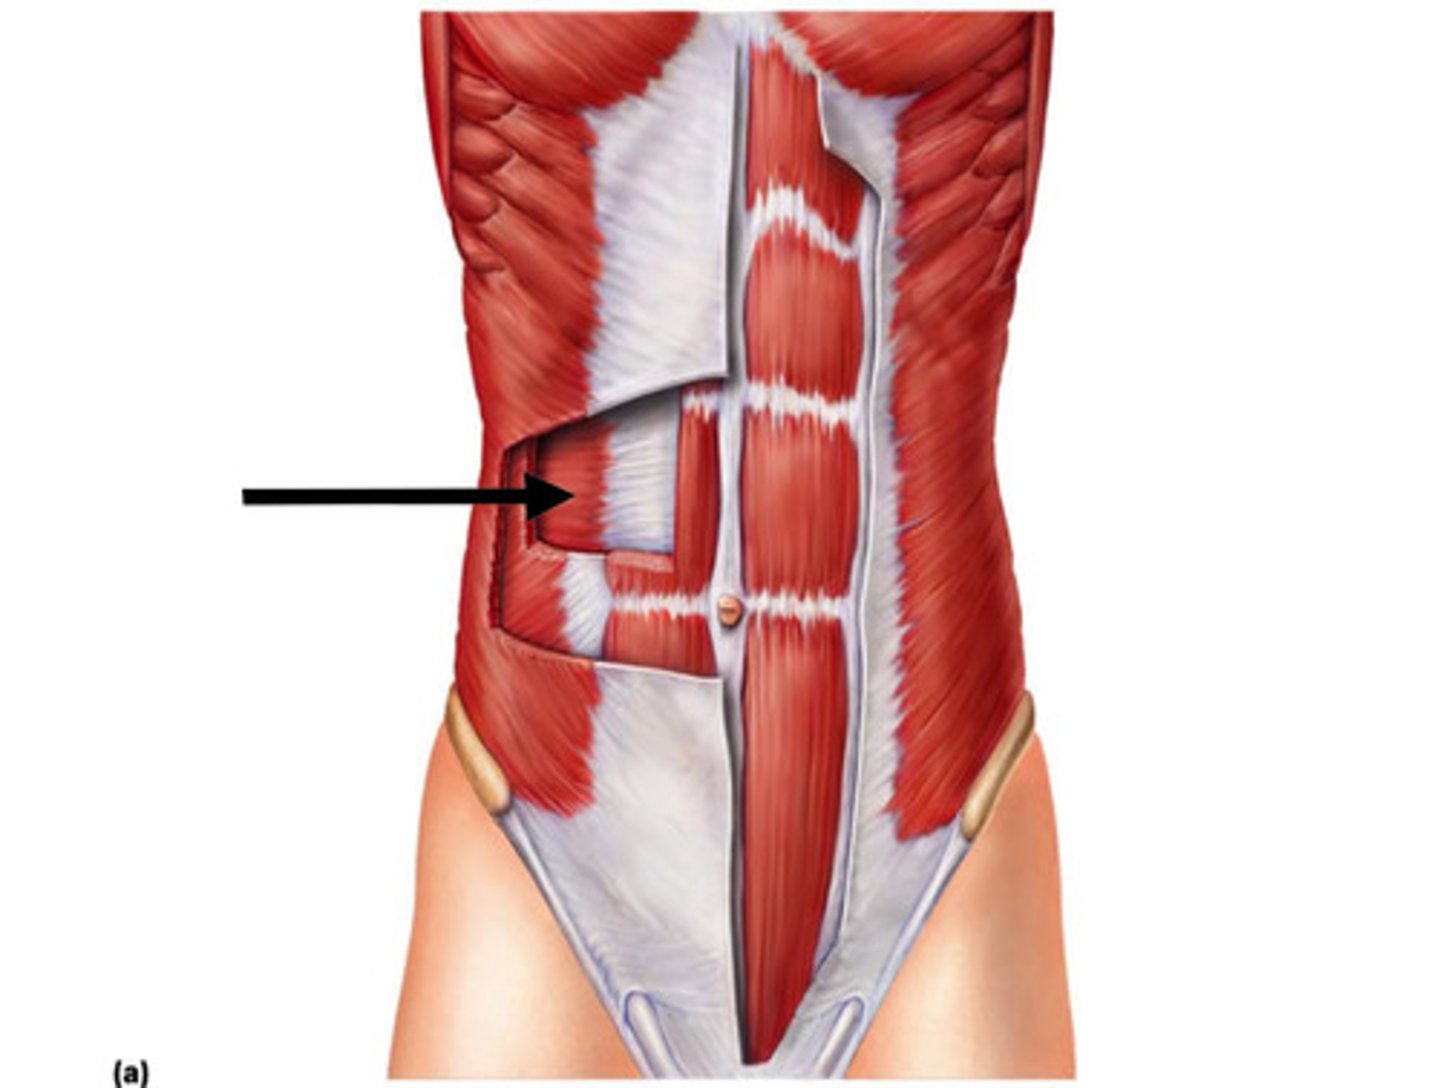

transversus abdominus

rectus abdominus

tendinous insertions

Aponeurosis

rectus sheath